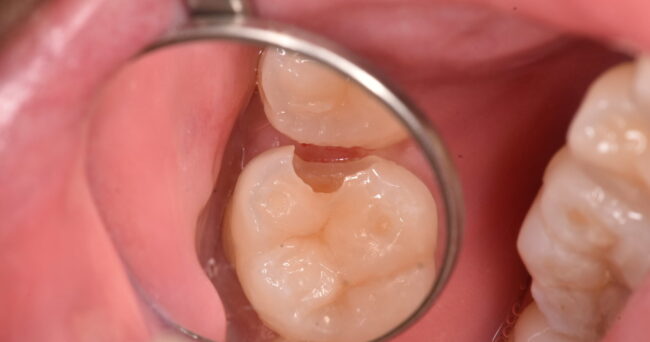

上の部分を除去するとこのような状態でした。

さらにとっていくと↑のようになっています。

きれいにすると、このようになりました。

正直、ゴールドの下で虫歯が進行している例をあまり見たことがありません。あけても何もない・・・そのような場合が多いのですが、今回のはなんと申し上げますか・・・